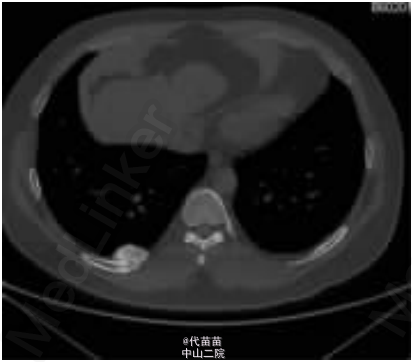

患者男性,40 岁。因体检发现肋骨肿块入院。患者无其它特殊症状,血生化检查基本正常,无放、 化疗史及Paget病史。CT检查示右侧第九后肋骨旁一团块状混杂高密度影,肿块边界尚清,位于肋骨表面,非髓内生长,向胸腔隆起,位于壁层胸膜与肋骨之间,与骨皮质有蒂相连(图 1、2)。临床考虑良性病变骨软骨瘤可能,遂行手术切除一段肋骨及表面肿块,送病理检查。 病理检查:眼观:送检肋骨1段,长9cm,宽2cm,骨表面隆起卵圆形肿块,4 cmX2 cmX2 cm 大小,质硬,切面灰白色,实性,与骨皮质有蒂相连,蒂部骨皮质浸润(图 3)。镜检:肿瘤由大量狭长且具平行排列倾向的高分化骨小梁构成,以编织骨为主,部分骨小梁已成熟为板层骨,大部分骨小梁周围缺乏成骨细胞被覆,部分区域已逐渐移行为有成骨细胞被覆的板层骨,瘤骨内可见骨重建过程中形成的粘合线,即所谓“Paget” 现象(图 4)。骨小梁间充满低细胞性纤维组织间质,梭形成纤维细胞形态温和,细胞核卵圆形,缺乏不典型性,部分肿瘤性骨小梁之间有脂肪髓形成,但无造血组织。肿瘤表面的骨样组织较幼稚,深部为相对成熟的粗大编织骨和板层骨(图 5),蒂部皮质和近皮质的髓腔内有局灶性肿瘤浸润(图 6)。肿瘤内含多灶性高分化软骨,软骨细胞排列紊 乱无极性,由于部分软骨位于肿瘤表面,故影像学和病理学类似骨软骨瘤改变。病理诊断:右侧第九后肋骨旁骨肉瘤。 骨旁骨肉瘤临床表现为骨表面缓慢生长的无痛性肿块,质硬,病程较长,可达数年。骨旁骨肉瘤预后较好,其5 年生存率达91% ,最佳治疗方案是大块肿瘤完整切除,切除范围应包括肿瘤周围的正常组织和软组织内的卫星病灶。若不完整切除则很容易复发。复发性肿瘤易发生去分化改变,称去分化骨旁骨肉瘤,其预后类普通型骨肉瘤,治疗原则和普通高级别骨肉瘤一致。 骨旁骨肉瘤可以说是骨肉瘤中的“异类” ,因为其不仅分化好,类似良性骨病,而且在骨表面生长,在病理诊断时须注意与以下三种良性骨病鉴别:(1)纤维结构不良。本例虽然部分肿瘤性编织骨呈不连续的字母状结构,在编织骨之间为高分化纤维,类似于纤维结构不良,但纤维结构不良是一 种纤维化生骨,伴有骨的成熟障碍,不会成熟为板层骨,也不会出现板层结构瘤骨在改建塑型过程中形成“Paget”现象。本例镜下见瘤骨比较成熟、 粗大,大部分相互连接成网,并有平行排列倾向,肿瘤表面骨样组织幼稚,深部较为成熟,并形成板层骨,成熟瘤骨内能见到“ 孕葬早藻贼” 现象。此外纤维结构不良均在髓内生长,不会在骨表面外生性生长,故影像学改变即可排除纤维结构不良。(2)骨软骨瘤。本例肿瘤内含有少量高分化软骨组织,由于部分软骨位于肿瘤表面,需与骨软骨瘤鉴别。骨软骨瘤蒂部的骨皮质常有缺损,肿瘤内的松质骨与宿主骨的正常松质骨相连续,二者相互融合。而骨旁骨肉瘤常环绕宿主骨在骨膜外生长,与髓腔不相通,肿瘤与骨密质之间有狭长的透亮带,即残存的骨膜;骨软骨瘤软骨帽下是由软骨化骨形成的松质骨小梁,骨小梁间隙内充满正常的造血性红髓或脂肪性黄髓,而缺乏骨旁骨肉瘤的成纤维细胞成分。同时骨旁骨肉瘤内的软骨组织、 结构和分布随意紊乱,缺乏骨软骨瘤明显的分层结构。(3)骨旁骨瘤。大多位于颅骨表面或副鼻窦内,分化成熟的骨小梁之间为脂肪细胞和小血管,缺乏纤维母细胞性间质。